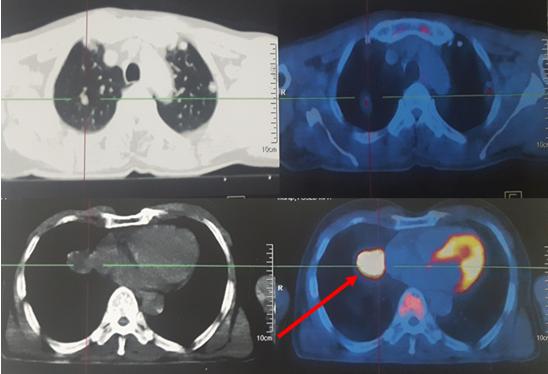

Chụp PET/CT đánh giá toàn thân:

Kết quả: Nhiều nốt tổn thương hai phổi kích thước max: 3,7x4,1cm, tăng hấp thu FDG, maxSUV: 14,1. Tổn thương não thùy thái dương đỉnh trái, kích thước 2,1x2,6cm, tăng hấp thu FDG, maxSUV: 8,6; có phù não rộng xung quanh. Không thấy tổn thương tái phát tại đại tràng.

Hình 2: Hình ảnh tổn thương di căn phổi trên PET/CT

Nhiều nốt tổn thương hai phổi kích thước max: 3,7x4,1cm, tăng hấp thu FDG, maxSUV: 14,1